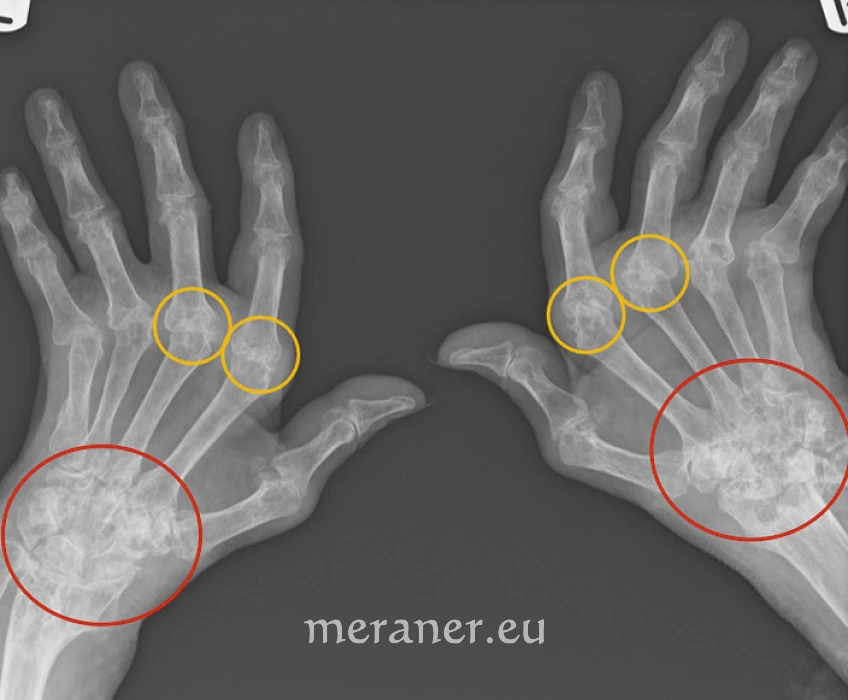

Röntgenbild einer RA mit destruktiver, symmetrischer Beteiligung v.a. der Gelenke zwischen Mittelhand- und Fingerknochen (gelbe Kreise), hier mit typischer Abweichung der Gelenksachse in Richtung Elle („Ulnardeviation“), und nahezu der gesamten Handwurzel (rote Kreise). Die Gelenksflächen sind durch multiple Knochenaussparungen („Erosionen“) als Ergebnis der chronischen Entzündung zerstört. Quelle: radiopaedia.org